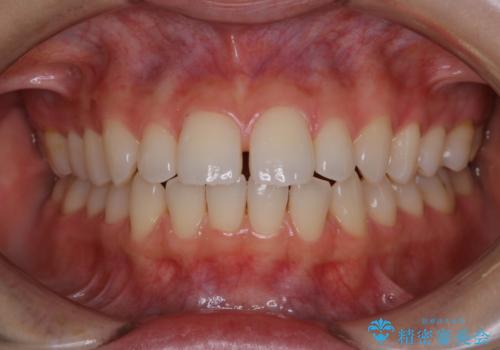

- これから矯正治療を始めていくため、きれいにしたいとのことでした。PMTC30分コースを行いました。

一見きれいに見える歯でも、染め出し(歯垢染色液)を使うとこのように歯と歯茎の境目や、歯と歯の間などに磨き残しがあることがわかります。歯磨きには、いつも気をつけているから磨き残しはナシと思っていても、実際完璧に磨ききることはなかなか難しいです。歯科医院にて、専門の機械で定期的なPMTCを行うことが大切です。

また、これから矯正治療が開始される方はなおさら歯磨きをマスターして、矯正治療中に虫歯や歯周病にならないようにケアする必要があります。